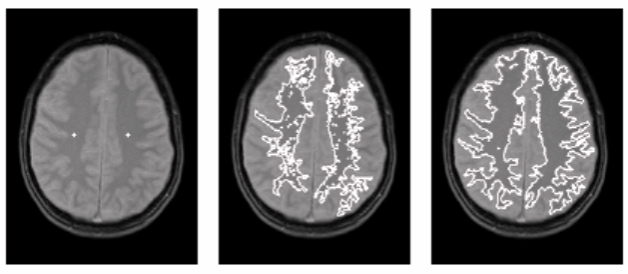

Fig. 2 (a) with seed marks (b) smallest region growing (c) expanded region growing Algorithm Steps

Region-growing methods rely mainly on the assumption that the neighboring pixels within one region have similar values. The common procedure is to compare one pixel with its neighbors. If a similarity criterion is satisfied, the pixel can be set to belong to the cluster as one or more of its neighbors. The selection of the similarity criterion is significant, and the results are influenced by noise in all instances.

This method takes a set of seeds as input along with the image. The seeds mark each of the objects to be segmented. The regions are iteratively grown by comparison of all unallocated neighboring pixels to the regions. The difference between a pixel’s intensity value and the region’s mean are used as a measure of similarity. The pixel with the smallest difference measured in this way is assigned to the respective region. This process continues until all pixels are assigned to a region. Because seeded region growing requires seeds as additional input, the segmentation results are dependent on the choice of seeds, and noise in the image can cause the seeds to be poorly placed.